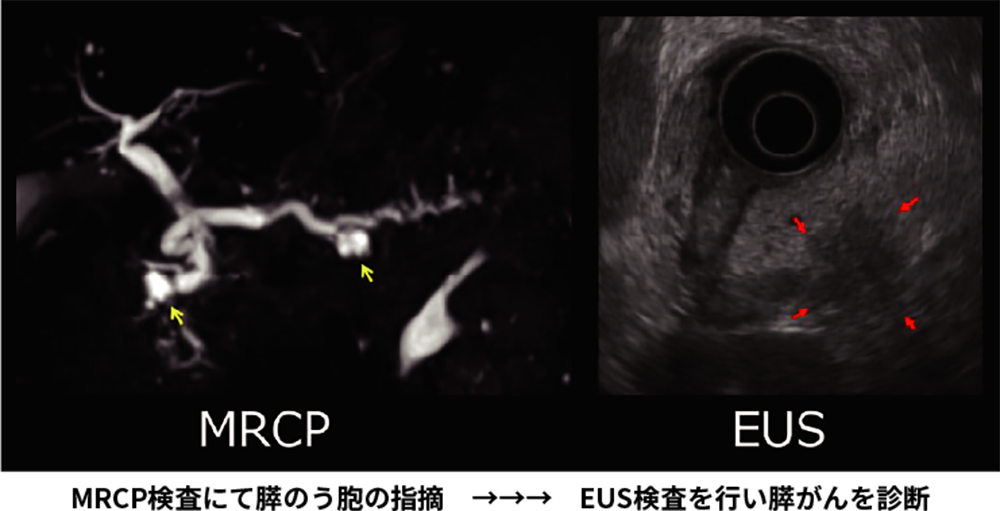

当院では、膵臓全体を詳細に観察することができる超音波内視鏡検査(EUS)や、MRIを用いて膵管・胆管を写し出すMRCP検査、細胞や組織の病理検査などにより診断を行います。